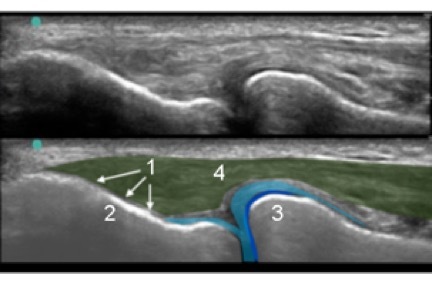

Elbow Common Extensor Tendon Anatomy Image

1. Tendon Insertion

2. Lateral Epicondyle

3. Radial Head

4. Common Extensor Tendon